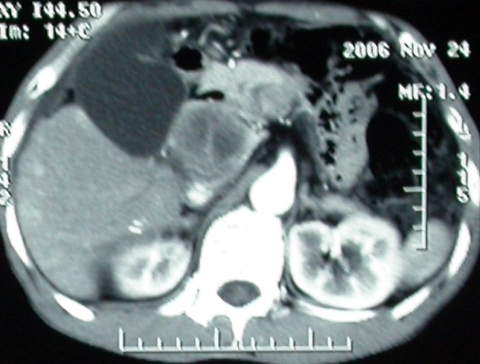

增强ct所见

ct表现:1,胰腺钩突后方肿块,不均强化,中心密度低,钩突及门静脉前移。2:肝右后叶不均强化灶,突出肝表面,3:胆囊明显增大,肝内胆管及肝总管内积气。4:腹腔内少量积液。

肝脏尾状叶肝癌(沿肝十二指肠韧带向下韧带内生长,门腔间隙外压增大),大结节性肝硬化,胆囊积脓,胆道感染。术中见肝外胆道2cm直径,肿瘤向前压迫胆管至扁平状态。